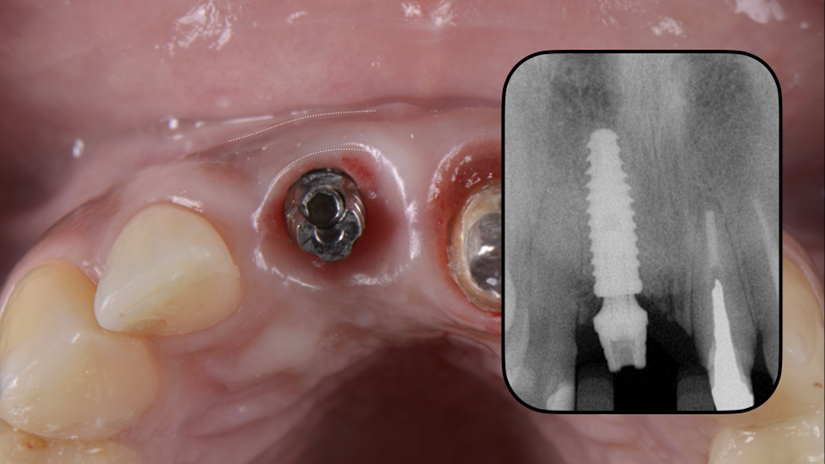

A região anterior da maxila é uma das áreas mais desafiadoras para reabilitação protética, principalmente quando se trata de implantes mal posicionados. Este caso clínico ilustra uma abordagem resolutiva para um implante vestibularizado na região do elemento 11, originalmente restaurado com um pilar reto tipo Smart de 4,5 mm, que inviabilizava a confecção de uma coroa parafusada esteticamente satisfatória.

A paciente apresentava queixas estéticas e funcionais. Após avaliação clínica e radiográfica, optou-se pela substituição do pilar reto por um pilar Ideale angulado de 17 graus e 3,3 mm de diâmetro. Esse componente mais estreito e angulado permitiu corrigir o eixo emergente da futura coroa, viabilizando o planejamento de uma prótese parafusada na região estética.